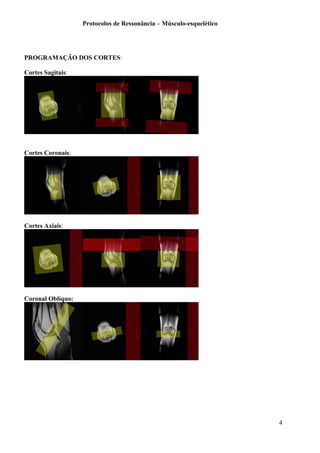

PROGRAMAÇÃO DOS CORTES:

Axiais: os cortes devem incluir a articulação acrômio-clavicular até o fim da glenóide

Coronais: os cortes devem necessariamente incluir o subescapular e o infraespinhal

Sagitais: os cortes devem iniciar no fim da cortical do úmero e devem prosseguir internamente.

Sagital T2 FS

Sagital T1. O sagital T1, com espessura de 5mm deve incluir o “Y” da escápula